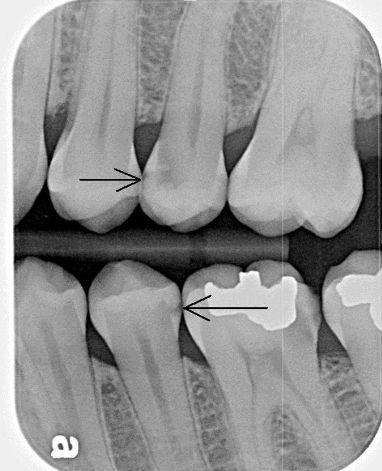

Tooth anatomy & cavities

Bacteria produce acidic byproducts

Acid removes minerals from teeth

• Caries (cavities)